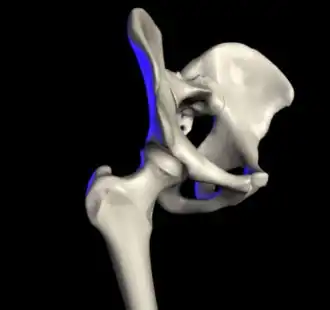

The hip joint or coxofemoral joint[5][6] is a ball and socket synovial joint formed by the articulation of the rounded head of the femur and the cup-like acetabulum of the pelvis.[7] The socket of the acetabulum is pointing downwards and anterolaterally. The socket is also turned such that the outer edge of its roof is more lateral than outer edge of the floor.[7] It forms the primary connection between the bones of the lower limb and the axial skeleton of the trunk and pelvis. Both joint surfaces are covered with a strong but lubricated layer called articular hyaline cartilage.

The cuplike acetabulum forms at the union of three pelvic bones — the ilium, pubis, and ischium.[8] The Y-shaped growth plate that separates them, the triradiate cartilage, is fused definitively at ages 14–16.[9] It is a special type of spheroidal or ball and socket joint where the roughly spherical femoral head is largely contained within the acetabulum and has an average radius of curvature of 2.5 cm.[10] The acetabulum grasps almost half the femoral ball, a grip deepened by a ring-shaped fibrocartilaginous lip, the acetabular labrum, which extends the joint beyond the equator.[8] The centre of the acetabulum (fovea) does not articulate to anything. Instead, it is lined with fat pad and attached to ligamentum teres. The acetabular labrum is horse-shoe shaped. Its inferior notch is bridged by transverse acetabular ligament.[7] The joint space between the femoral head and the superior acetabulum is normally between 2 and 7 mm.[11]

Capsule

Proximally, capsule of the hip joint is attached to the edge of the acetabulum, acetabular labrum, and transverse acetabular ligament. Distally, it is attached to the trochanters of the femur and intertrochanteric line anteriorly. Posteriorly, it is attached to a junction between medial two-thirds and lateral one-third of the femoral neck,[7] one finger breadth away from the intertrochanteric crest.[24] From its attachment at the femoral neck, the fibres of the capsule reflected backwards towards the acetabulum, carrying retinacula vessels supplying the femoral head.[7] The part of femoral neck outside the capsule is shorter in front than posteriorly.[24]

Ligaments

The hip joint is reinforced by four ligaments, of which three are extracapsular and one intracapsular.

The extracapsular ligaments are the iliofemoral, ischiofemoral, and pubofemoral ligaments attached to the bones of the pelvis (the ilium, ischium, and pubis respectively). All three strengthen the capsule and prevent an excessive range of movement in the joint. Of these, the Y-shaped and twisted iliofemoral ligament is the strongest ligament in the human body. It has a tensile strength of 350 kg.[24] Iliofemoral ligament is a thickening of the anterior capsule extending from anterior inferior iliac spine to intertrochanteric line.[7] Ischiofemoral ligament is the thickening of posterior capsule of the hip and pubofemoral ligament is the thickening of the inferior capsule.[7] In the upright position, iliofemoral ligament prevents the trunk from falling backward without the need for muscular activity, thus preventing excessive hyperextension. In the sitting position, it becomes relaxed, thus permitting the pelvis to tilt backward into its sitting position. Ischiofemoral prevents excessive extension and the pubofemoral ligament prevents excess abduction and extension.[26]

The zona orbicularis, which lies like a collar around the most narrow part of the femoral neck, is covered by the other ligaments which partly radiate into it. The zona orbicularis acts like a buttonhole on the femoral head and assists in maintaining the contact in the joint.[24] All three ligaments become taut when the joint is extended - this stabilises the joint, and reduces the energy demand of muscles when standing.[27]

The intracapsular ligament, the ligamentum teres, is attached to a depression in the acetabulum (the acetabular notch) and a depression on the femoral head (the fovea of the head). It is only stretched when the hip is dislocated, and may then prevent further displacement.[24] It is not that important as a ligament but can often be vitally important as a conduit of a small artery to the head of the femur, that is, the foveal artery.[28] This artery is not present in everyone but can become the only blood supply to the bone in the head of the femur when the neck of the femur is fractured or disrupted by injury in childhood.[29]